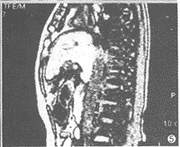

19例中,肝脏增大18例(95%),尾叶增大14例(74%)。14例(74%)肝脏信号不均,T2WI呈斑片状稍高信号,T1WI呈稍低信号且较明显(图1~3)。7例(37%)显示下腔静脉入右心房处阻塞;4例(21%)下腔静脉内有血栓影,表现为T1WI呈等信号,T2WI呈稍高信号;下腔静脉肝后段裂隙样狭窄10例(53%)。19例(100%)均显示肝静脉狭窄或阻塞,其中累及左肝静脉15例,中肝静脉13例,右肝静脉11例。17例(89%)见有肝内侧支血管呈“逗号”样或迂曲、走行无规律的血管影,5例(26%)显示有副肝静脉,呈粗大的血管影自肝右叶连于下腔静脉的右侧壁(图4~6)。17例(89%)见有肝外侧支血管,其中7例腹壁静脉曲张,14例(74%)有粗大的奇静脉和/或半奇静脉影,膈下静脉曲张3例,胃底静脉曲张3例。脾脏增大16例(84%),7例(37%)有腹水。

图4 T2WI显示副肝静脉汇入下腔静脉,脾脏增大

图5 矢状位显示下腔静脉入右房处节段性阻塞

对于肝内侧支血管的显示CT不如超声,但MRI则能达到与超声相似的效果[5,7]。肝内侧支血管表现为多发的“逗号”样异常信号或弯曲、粗大,异常走向的血管影连接于肝静脉之间,不同于正常的肝静脉表现。本组5例显示有副肝静脉,均出现在第2肝门下方,表现为肝右叶与下腔静脉右侧壁之间粗大的血管影。本组14例有奇静脉、半奇静脉扩张,出现在膈脚后呈粗大的血管影。膈下静脉、胃底静脉、腹壁静脉也可迂曲扩张。本组结果说明MRI对于肝外侧支血管的显示优于超声,与静脉造影相似。